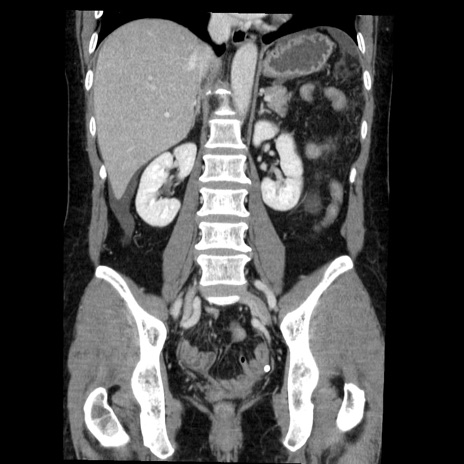

症例6(冠状断像)

【症例】50歳代女性

【主訴】下腹部痛

【現病歴】本日朝より下痢2回あり。 昼食を食べた後、嘔吐3回、下腹部痛認め、症状軽快せず、当院救急搬送。

最終食事:本日昼(生ものなし)。 昨日の夜、刺身を食ぺたとのこと。周囲に同様の症状の者なし。普段、排便は毎日あるとのこと。

【既往歴】卵巣癌術後(8年前に当院で卵巣摘出)

【身体所見】 意識清明、腹部:平坦、腸蠕動音→、やや硬、下腹部自発痛・圧痛あり、反跳痛あり、筋性防御なし。

【データ】WBC 16000、CRP 0.01